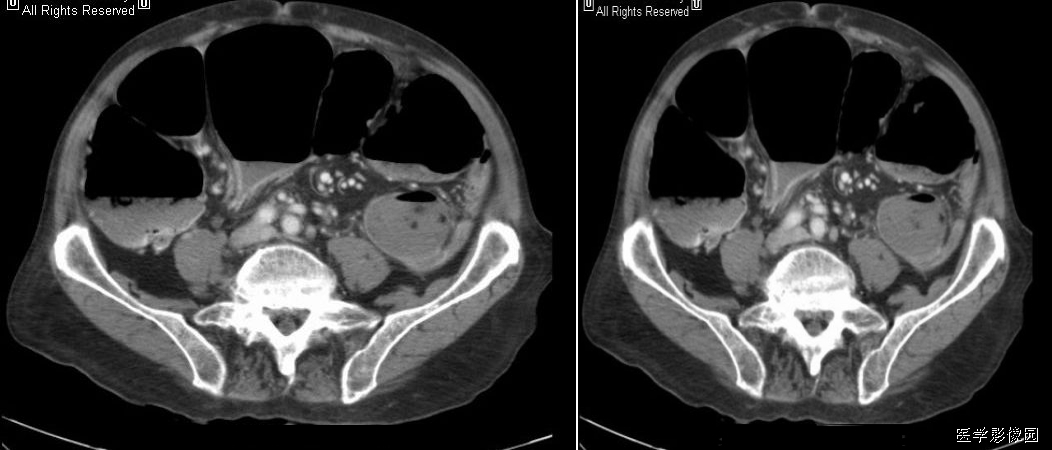

1、靶征(肠套叠)

是肠套叠最常见的特征性CT征像,为肠套叠长轴与CT扫描层面垂直时的表现,反映了套叠的各层肠壁、肠腔及肠系膜间的关系。典型排列为自外向内分别代表鞘部外层肠壁、鞘部肠腔内造影剂、鞘部内层肠壁、偏心性套入部肠系膜、套入部肠壁、套入部肠腔内造影剂。

肠套叠指:一段肠管及与其相连的肠系膜(套入部)被套如其相连的一段长管内(鞘部),导致肠内容物通过阻碍。婴儿由于大肠与小肠管径之比例相差大。故小肠易陷入大肠而被套牢。少数肠套叠可能来自某些器质性病变如美凯尔憩室、肠息肉、异位胰腺小结、血管瘤、异物、复制肠管、淋巴增生、肿瘤、寄生虫等,其中以美凯尔憩室最多,过敏性紫斑也常会合并肠套叠,大于2岁的小孩发生肠套叠,一定要考虑到这些病变。大于5岁的病例中,则以淋巴瘤为最多;成人肠套叠小肠多见,常伴发良性病变;结肠型肠套叠则更多由恶性病变继发。良性病变有脂肪瘤、平滑肌瘤、血管瘤、神经纤维瘤、腺瘤样息肉、美克尔憩室、术后粘连机场动力性病变等;恶性病变有转移瘤、腺癌、类癌、淋巴瘤及平滑肌肉瘤等。由于肠套叠长轴与CT扫描层面的角度不同,表现各异。

如扫描层面和迂曲的肠道相平行时,表现为彗星尾征或肾形征:即套叠近端肠系膜血管牵拉聚拢的征象。一般情况下,慧星尾征均与肾型肿块相伴出现。该肾形肿块为套鞘部游离缘与套入部近端肠管及肠系膜的CT斜切面图像,其中游离的套鞘呈弧形围绕套入部,形状若肾轮廓外形,而套入部近端肠管、肠系膜形状若肾蒂。此时,所谓慧星尾征的组成还应包括套入近端肠管。如果套叠的肠管与CT扫描垂直,则呈靶形征,即肿块影表现为圆形或类似环形。通常在肿块内可分辨出层样结构,推测可能是继发于套入部和鞘部间的液体或是肠壁水肿造成密度对比,类似同心圆形;当套入部肠壁显著水肿坏死或套入部肿瘤周围浸润累及肠系膜,肠系膜血管及脂肪、套叠时间较长,套入部系膜血管受挤压时,静脉血液回流障碍,套入部肠壁充血水肿、变硬,形成不完全性肠梗阻,套叠以上肠管蠕动增强,可引起代偿性肠管扩张肥厚,并可见肠系膜连同其血管纠集、扭曲,形成“漩涡征”。